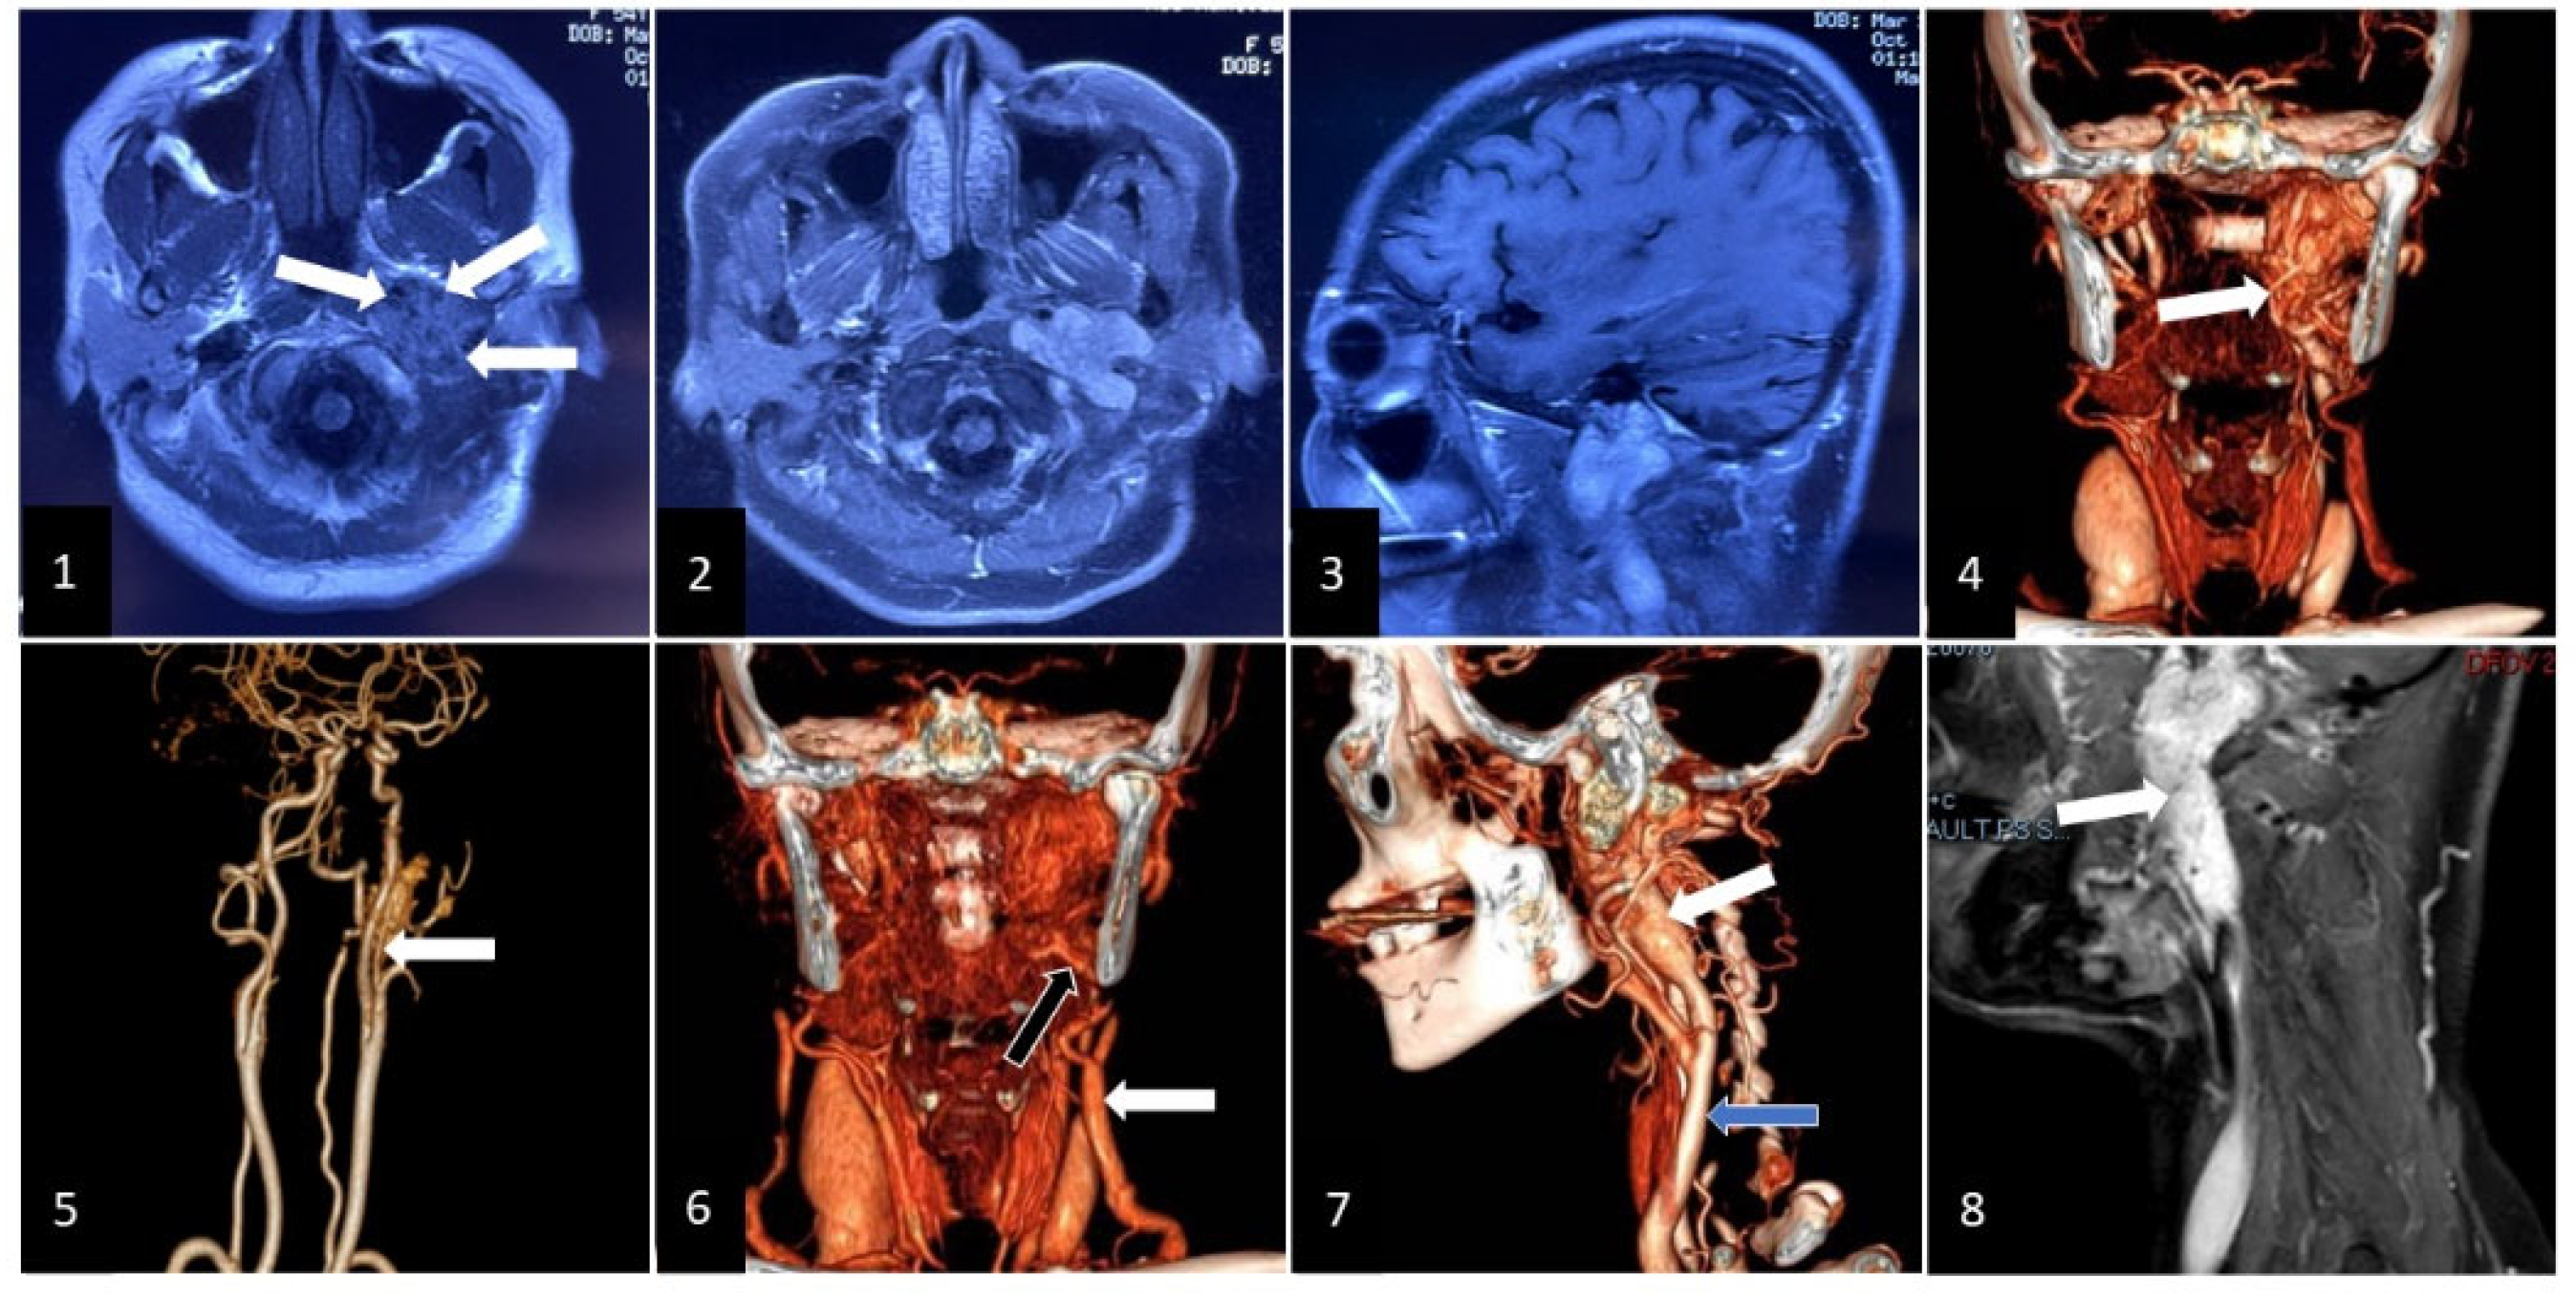

2. Clinical Case